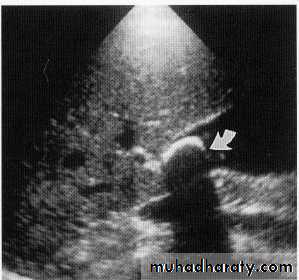

Leiomyoma EUS